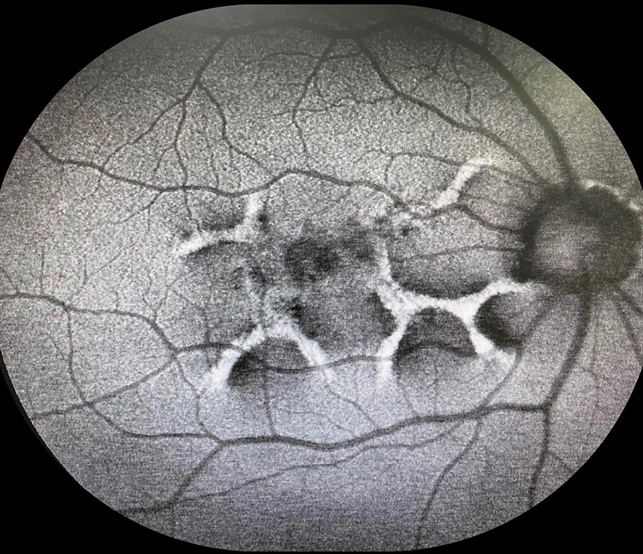

Pattern Dystrophy Slide 1 Retina Image Bank

Pattern Dystrophy Slide 2 Retina Image Bank

Pattern Dystrophy Retina Image Bank